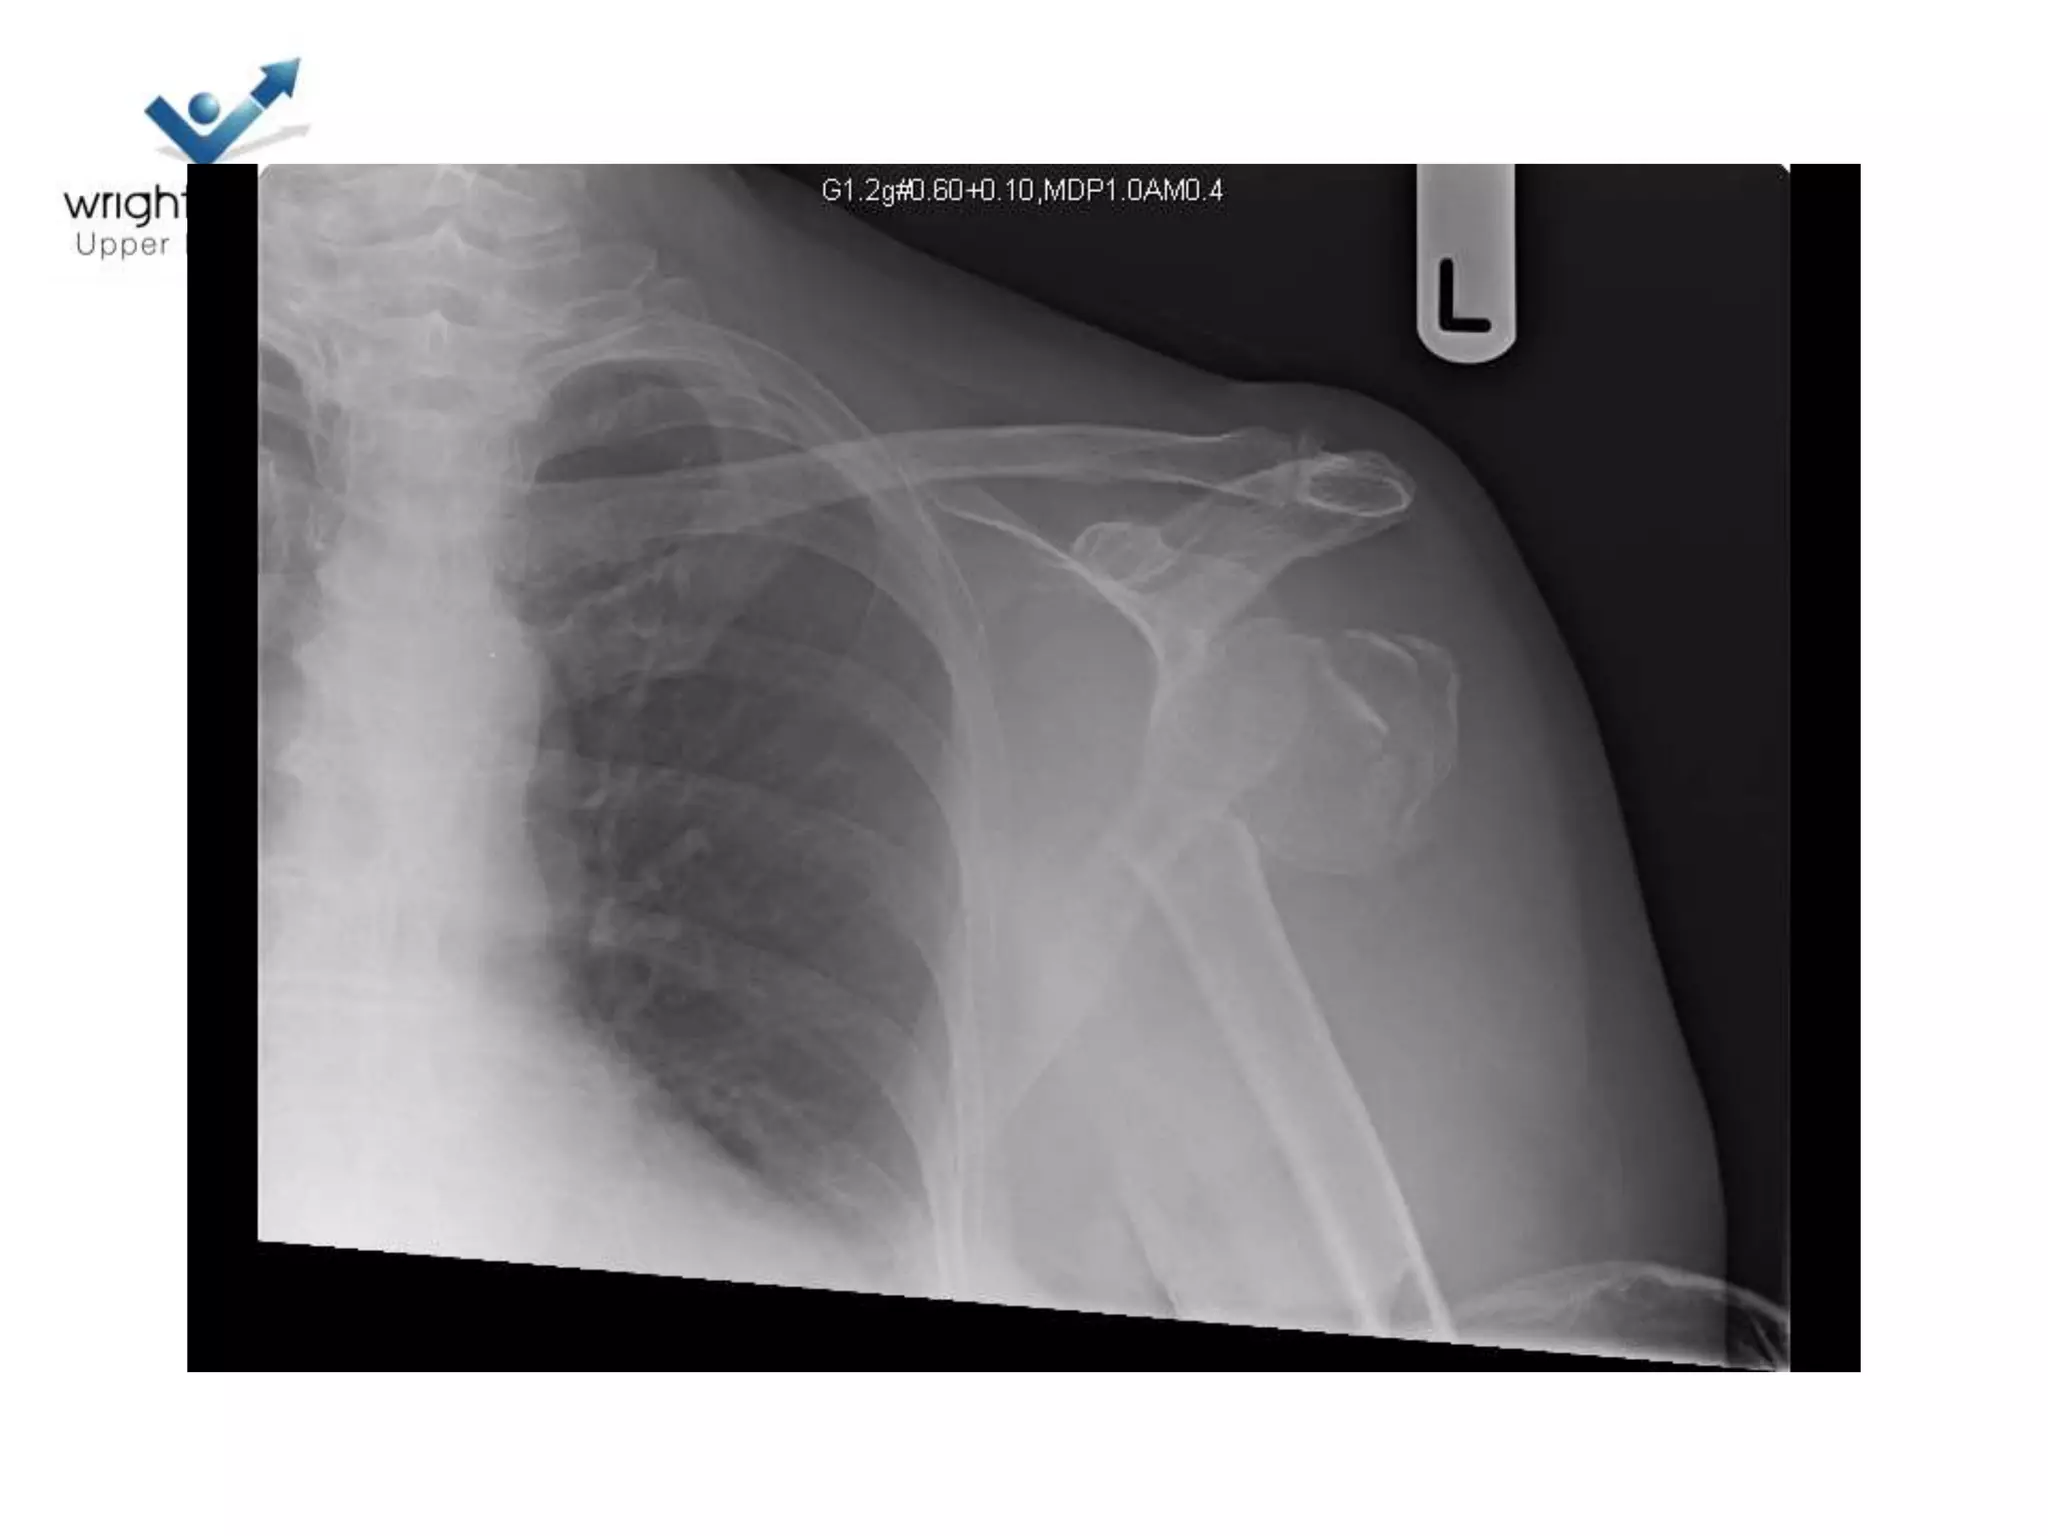

Case discussions

2 Next

3 Next